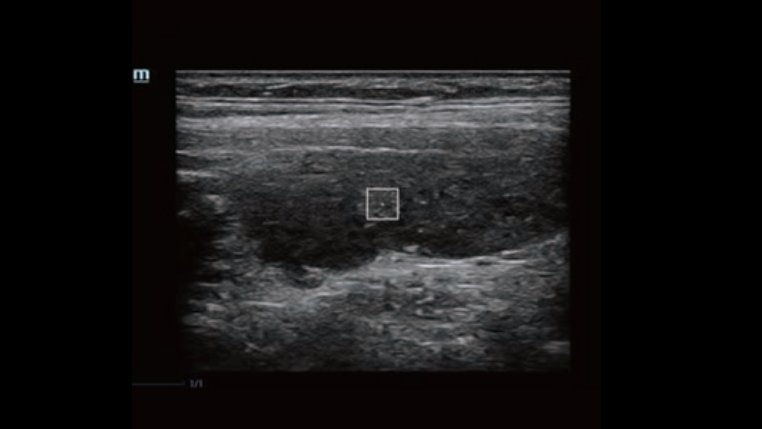

Dynamic Pixel Focusing technology allows the Resona 6 to achieve extreme uniformity in pixel level throughout the whole field of view. Now there's no need to adjust the focal positions to achieve uniformity across patient exams.

By retrospectively analyzing complete channel data stored in channel data memory, the Resona 6 is able to intelligently choose the optimal sound speed to improve image accuracy even with tissue variation, allowing for adaptive tissue-specific optimization.

HD Scope: By processing channel data retrospectively, HD Scope enables tissue-specific enhancement with improved detailed information and image contrast on specific region of interest.